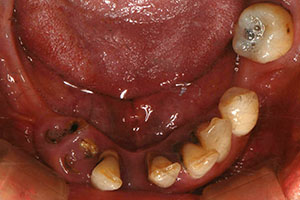

치료증례 전후사진

Before & After